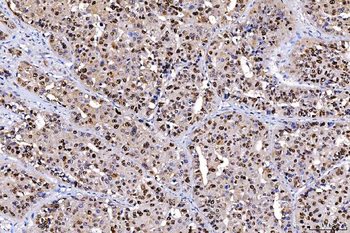

![Anti-FEN1 [SAIC-21C-4]](/images//pub/media/catalog/product/NewWebsite/35/orb1089994_1.png)

![Anti-FEN1 [SAIC-21C-4]](/images/pub/media/catalog/product/NewWebsite/35/orb1089994_2.png)

![Anti-FEN1 [SAIC-21C-4]](/images/pub/media/catalog/product/NewWebsite/35/orb1089994_3.png)